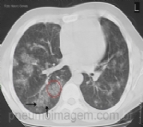

DESTAQUES DO ERS2016: HEMORRAGIA ALVEOLAR DIFUSA (HAD)

A HAD é uma doença rara, mas muito grave. Os achados típicos à TC de tórax são opacidades bilaterais e difusas em vidro fosco, frequentemente dos ápices até os ângulos costofrênicos. A terça parte dos pacientes não tem hemoptise à apresenta...